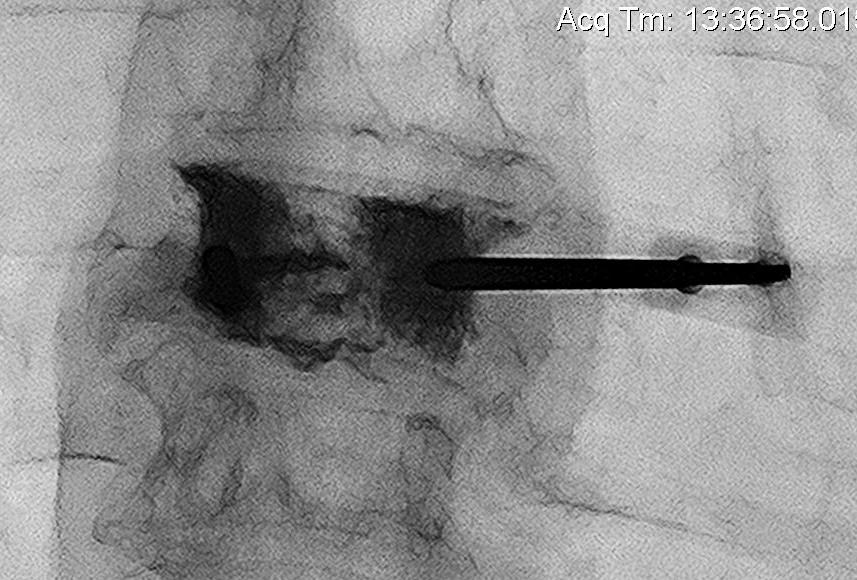

Technique

Percutaneous

- trochar into pedicle under fluoroscopy

- injection PMMA